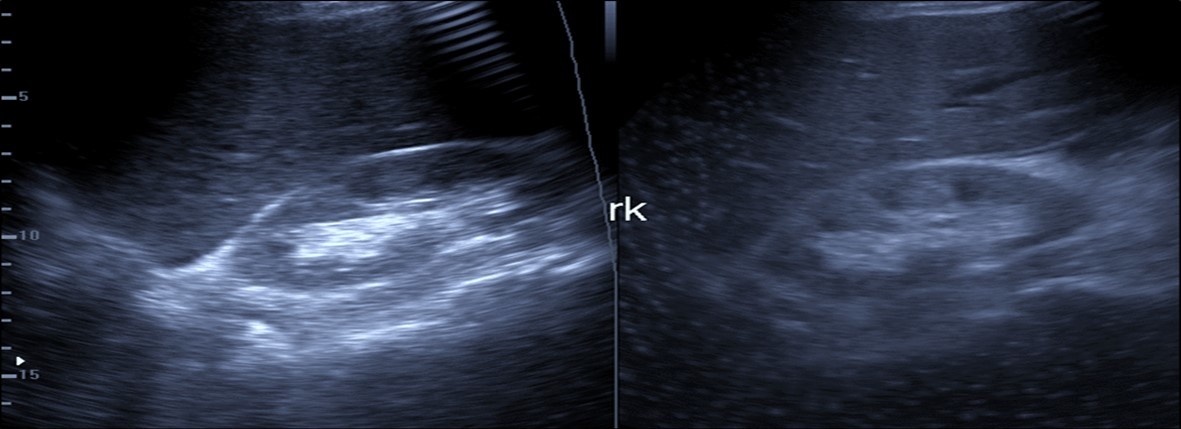

Abdominal ultrasound may revealed any of the followings:-Mild hepatomegaly with echogenic parenchyma and ascites in cases with hepatic impairment (Figure 4, Figure 5) ,thick walls of gall bladder with mildly dilated Common bile duct suggesting of biliary stasis and cholecystitis (Figure 6) .Abnormal renal echogenicity (Figure 7), suprarenal gland enlargements with heterogeneous texture ,splenic wedge shape area of hypoechogenicity ,thickened walls of bowel mainly the rectosigmoid region ,dilated bowel loops with free peritoneal fluid, and gases in the bowel wall with mesenteric and portal vein gases suggesting of bowel wall infarction13.

Figure 7.Patient with Covid-19 showing an echogenic kidney (rk) by ultrasound.

3. Increased renal parenchymal enhancement with acute tubular injury versus collapsing glomerulonephropathy and focal areas of reduced cortical enhancement associated with small renal vessels microthrombosis.